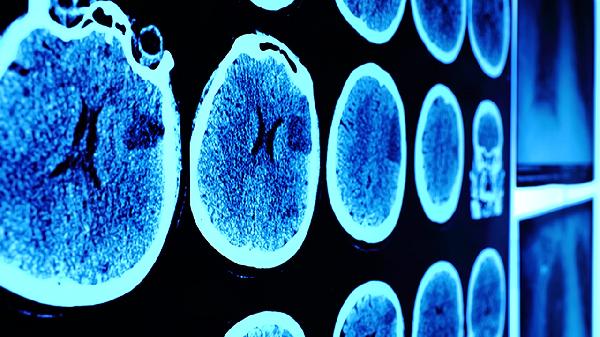

儿童脑震荡可能会表现出头痛、呕吐和眩晕等症状,通常不需要特殊治疗。脑震荡是由于外力作用于头部,导致暂时性的功能障碍,通常不会造成永久性的神经损伤。大多数情况下,孩子可以自行恢复,不需要额外的医学干预。不过,如果孩子出现意识丧失、持续性呕吐或行为异常等症状,这可能预示着颅内压力增高或其他并发症的风险,建议及时就医。